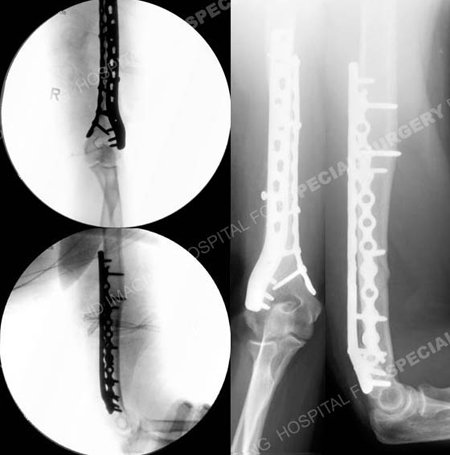

Intraoperative fluoroscopic AP and lateral images reveal adequate reduction and alignment (left images) and radiographs at 6 months reveal a healed humerus fracture in excellent alignment with maintenance of reduction and fixation (right images).